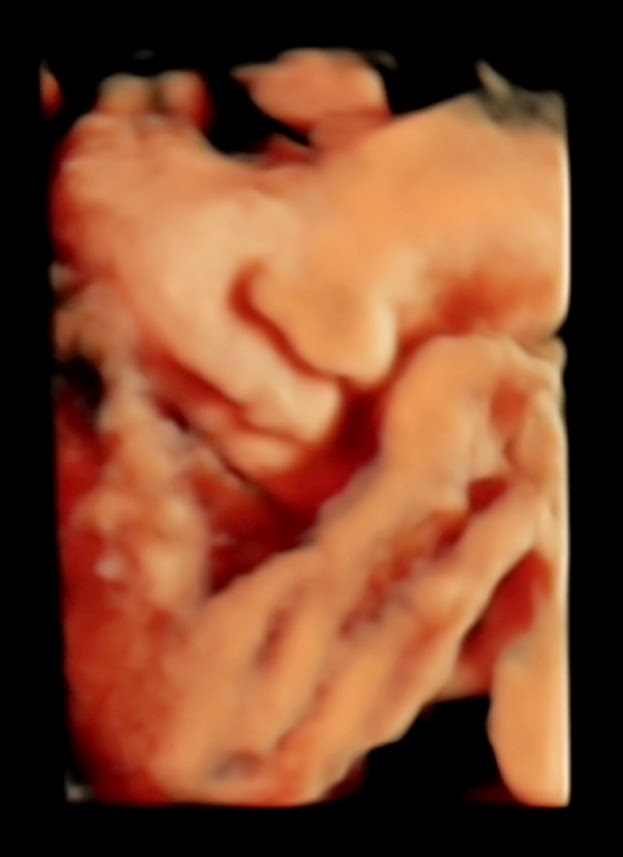

4D HD Scan〜4Dエコー〜

先週の事になりますが、赤ちゃんの4Dスキャンに行ってきました。

ロンドンでは、病院でのエコーは、異常がない場合は妊娠中二度のみ。

9ヶ月に入り、赤ちゃんの記念にもなるようにと、プライベートのクリニックで4Dのエコー&ビデオを撮ってもらう事にしました。

こちらが4DかつHDで撮ってもらった写真。

とってもぷっくりしたお顔に、思わずビックリ!!

前回のエコーは、白黒だったし、4Dの鮮明さに驚きの連続でした。

終始手を動かしたりしてましたが、それでも寝ている様子で、常に手を顔の近くで隠すような体勢だったので、なかなかうまく撮れず・・・。

スタッフの方も、何とか良い映像を撮ろうと、途中休憩を入れて15分ほどお外を散歩したりして、赤ちゃんが起きてくれるように試みたのですが、やっぱり手はそのまま。(^ ^)

よく考えると、私もこんな風に寝る事が多いな〜。

最後に撮れた一枚は、とっても可愛かった〜〜❤

お口をモグモグ動かして、なんだかニッコリしてくれたのか、何か楽しい夢を見てるのか、とにかく穏やかそうなお顔でした。

口も鼻も、9ヶ月でこんなにしっかりするものなんですね。

1720gまで体重も増えていました。

お外の世界に出るために、きっと一生懸命準備してるんでしょうね♪♪

私達がお腹の中にいた頃は、エコーなんてなかったのに、時代はすっかり進化したものです。

私にとってもパコちゃんにとっても、貴重な体験となりました。

あと一ヶ月と少し、一緒に頑張ろうね!!